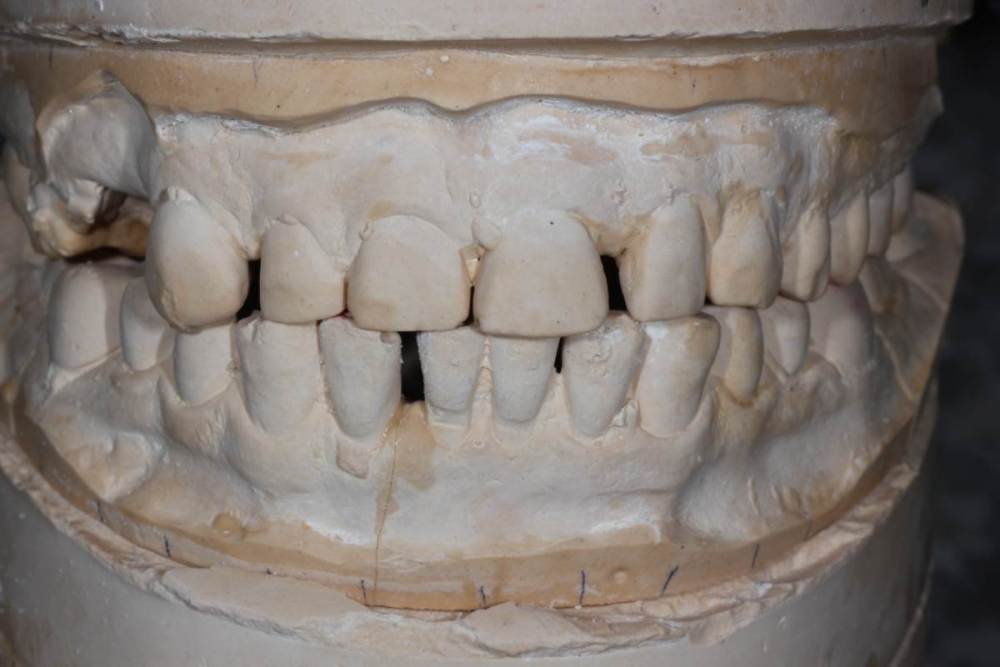

Для сравнения ситуация до:

1118463997_ICP(2).thumb.JPG.6ea5ace5a0ac58ccc721805c17d53dc0.JPG